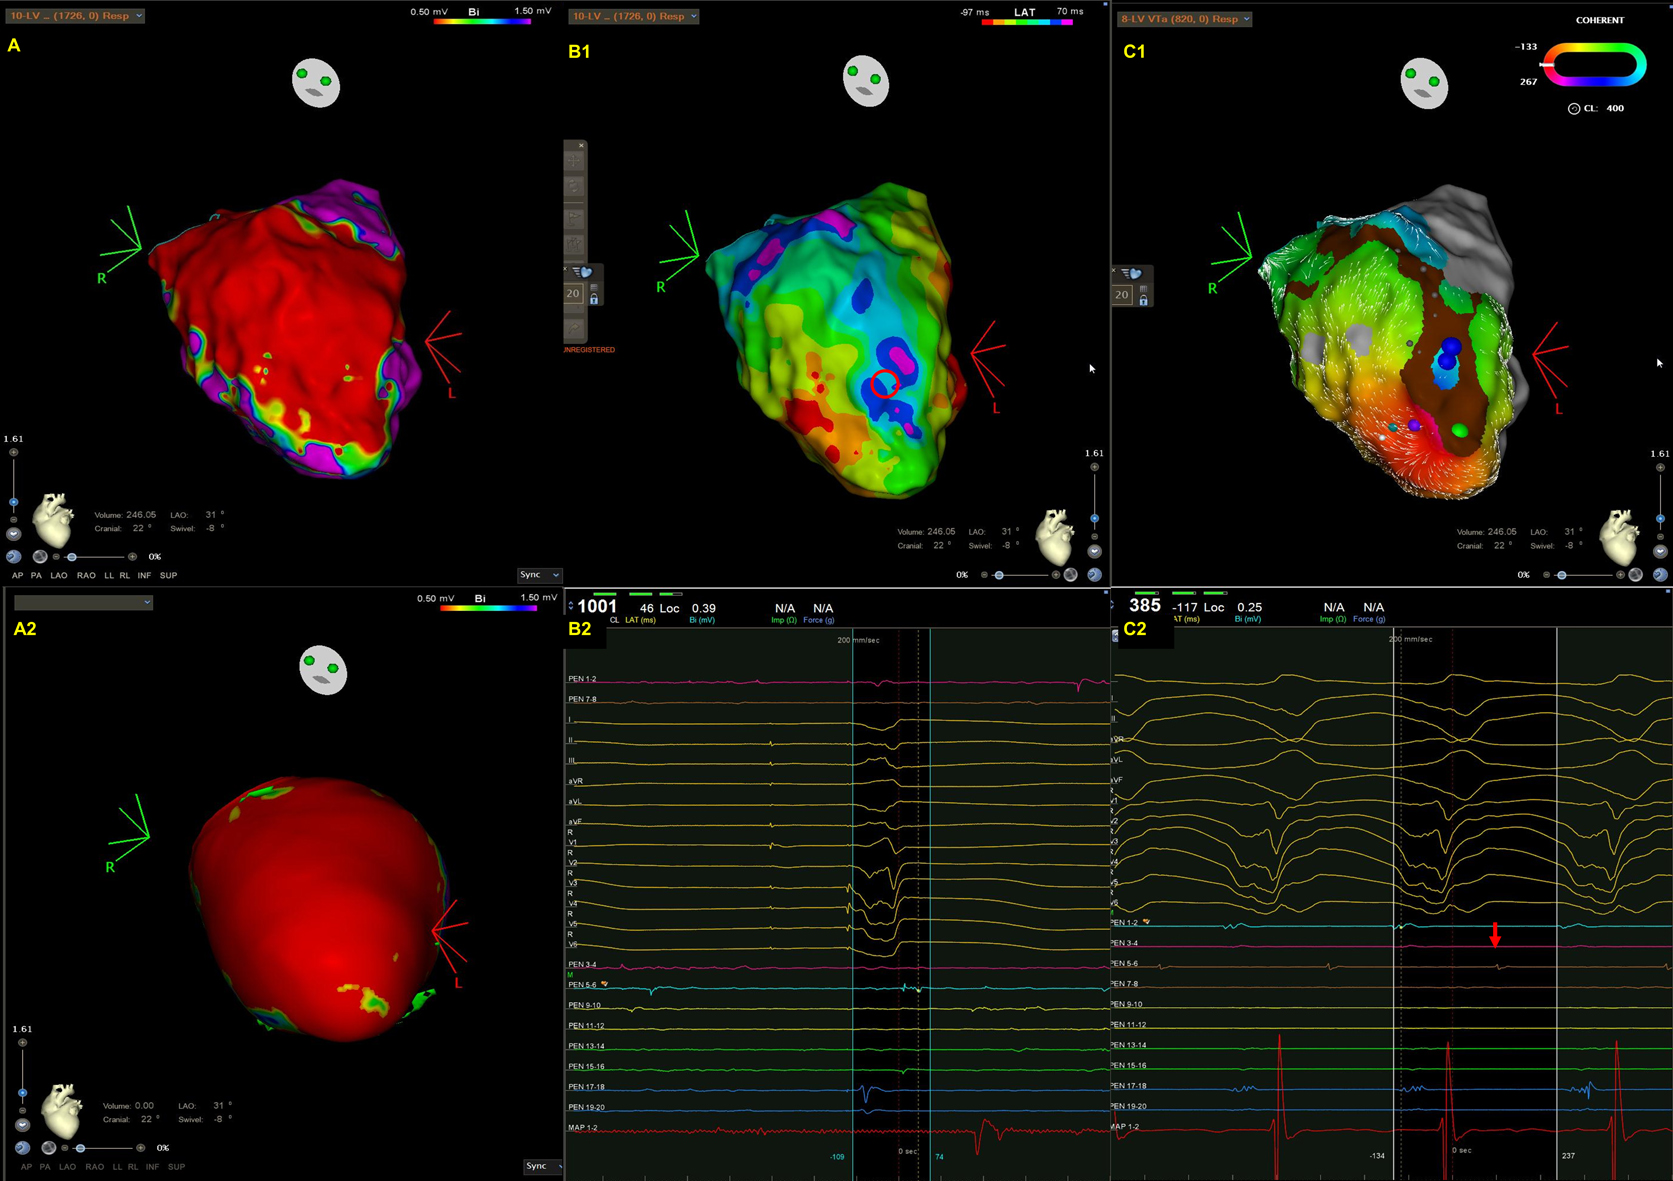

Fig. 1.A representative case of intramural ventricular tachycardia (VT) in a patient with arrhythmogenic left ventricular cardiomyopathy (ALVC) caused by titin mutation. Endocardial bipolar voltage (A) and preprocedural cardiac MRI (A2) revealed extensive scarring along the anterior septum and anterior wall, extending from the base of the LV to its apex. The scars identified by cardiac MRI are larger than those detected by endocardial bipolar voltage mapping owing to the presence of intramural scarring. (B1–2) An isochronal late activation map (B1) created by annotating the latest component of bipolar electrogram during right ventricular pacing and fractionated potential (B2) recorded within scar (red circle in B1). In particular, an isochronal crowding region was noted close to the scar border in the LV apex. (C1–2) VT activation map (C1), VT morphology and diastolic potential (C2). VT cycle length was 385 milliseconds with a left bundle branch block morphology and superior axis. The VT activation map (from red, orange, yellow, green, blue, indigo, to violet) demonstrated an incomplete circuit characterized by an activation gap (parts of the blue and violet are missing) within the endocardium. The mid-diastolic potential (red arrow, C2) was recorded at the blue dot site (C1). After radiofrequency energy was applied to the blue dot area, VT was terminated.

As opposed to ARVC, where the arrhythmogenic substrate is typically located at the triangle of dysplasia in the RV [16], ALVC exhibits fibrofatty infiltration along the LV posterobasal and anterolateral walls [21] (Fig. 1). Since the LV wall is thicker than that of the RV, the arrhythmogenic substrate tends to stay in subepicardial layers without expanding to the subendocardium [1, 22].

Ideally, the most important step is to induce clinically documented VT. We applied rapid ventricular pacing and programmed stimulation of up to three extra-stimuli from the RV apex and/or RVOT to induce VT in our laboratory [12, 81, 82]. When VTs are induced, QRS morphology and cycle lengths, either as documented by 12-lead ECG or intracardiac defibrillator (ICD), have been compared with those of clinically documented VTs [12, 81, 82]. Once the VTs are induced and mappable, activation mapping and entrainment mapping are employed to illustrate the VT circuits and identify critical isthmuses [83, 84]. It is noteworthy that since three-dimensional circuits are frequently observed in VTs and epicardial substrates are frequently observed in ACMs, an incomplete circuit characterized by an activation gap (Fig. 1) or endocardial/epicardial focal centrifugal activation pattern could be discovered [10]. Therefore, entrainment from the earliest activation sites and the adjacent scar is required to determine the potential exit or surrogate of reentrant circuits [85].